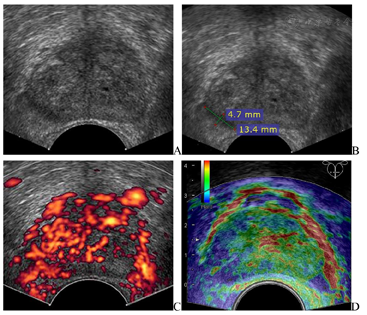

(1)经直肠超声(图1):前列腺右侧周缘区低回声结节,大小约13 mm×5 mm,无明显向前列腺包膜外隆起;结节内部血流信号丰富;弹性成像该低回声质地硬,评分4分。超声诊断:前列腺右侧周缘区实质性结节,前列腺癌可能,建议超声引导下穿刺活检。